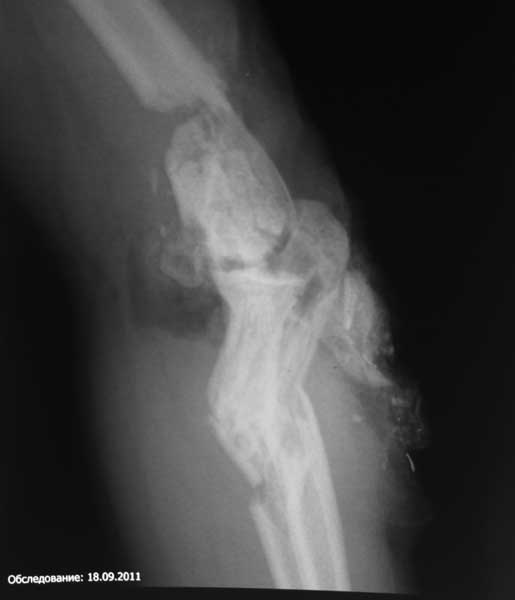

Оперировали в четверг. Начали с лучевой кости. Легко фиксировали её TEN закрыто ретроградно. Приняли решение ревизовать сустав задним доступом. Открытии локтевую кость , выполнен остеосинтез ульнарным блокируемым гвоздём. Продолжили разрез на плечо. Отломки мыщелков смещены во всех мыслимых направлениях, ротированы, практически лишены связи с мягкими тканями и окружены хрящевой мозолью. Имеются фиброзные сращения отломков плеча с проксимальными отделами костей предплечья. Проксимальный фрагмент плеча упирается в суставные поверхности предплечья. Осумкованные остатки одежды. Операционная картина смещения отломков не позволяла сделать «приблизительную репозицию» - для минимального сближения отломков их было необходимо полностью мобилизовать. Мыщелковые отломки собраны в единый блок, фиксированы спицами и финтами. Сухожилие трицепса сохранило связь с локтевым отростком по наружной поверхности. Локтевой нерв из заднего доступа выявить не удалось. Внутренний надмыщелок - где то сильно спереди. Топографически по краю локтевой кости удалось обнаружить атрофичный тяж, напоминающий раздавленный нерв. С ревизией не упорствовали – повреждение нерва должно быть очень протяжённым и слишком выражен рубцовый процесс с этой зоне. В дальнейшем надо, видимо, будет делать «вставку». После собирания мыщелков состыковали полученный конгломерат с проксимальной частью плеча. Фиксация реконструктивной LCP за наружный, самый крупный фрагмент в районе головки мыщелка. В дефект метафиза – гранулированный ‘’CronOS’’ + ванкомицин. После тщательных санаций и лаважей перешли к закрыванию раны, намереваясь смонтировать Илизарова. Немедленно выяснилось, что как раз на самой середине раны, над локтевым отростком края кожи сводятся с критическим натяжением. Кости предплечья при малейшем движении в суставе вывихивались кнаружи, что потребовало фиксации спицей сустава (луч-головка). Разгибание в суставе также не давало возможности ушить кожу без натяжения. Причиной помехи виделось изменение взаимоотношений тканей и рубцовый конгломерат по передней поверхности плеча и локтевого сустава, после репозиции отломков сместившийся кпереди. Операционный отёк был минимален. Сразу родилось запоздалое соображение. Было бы не лишним перед открытым вмешательством наложить дистракционный аппарат, дать дозированное удлинение за предплечье и создать запас пространства, выполняя некоторый «таксис» отломков плеча, а не идти сразу на прямую репозицию. Почему то задним умом думается, что это значительно бы облегчило работу с мягкими тканями. Рана была закрыта с натяжением краёв при помощи эластичных нитей на степлерных скобках. В таких условиях пришлось отказаться от монтажа илизаровского АВФ и активизации сустава – теперь рану надо закрывать этапно. Смонтирован ExFIX c шарниром по осевой спице – сама спица удалена. Наложен VAC на рану. Оставили катетер в сплетении, обезболивали 3 суток маркаином.

Никакого удовлетворения вмешательство не принесло. Сомнений в необходимости открытого вмешательства и реконструкции анатомии - ретроспективно прибавилось. А тут ещё и Каддафи убили…

Ну и ещё, а после операции можно сделать рентген так, чтобы самим было понятно, где кости, а где металл? Как минимум, некорректно!